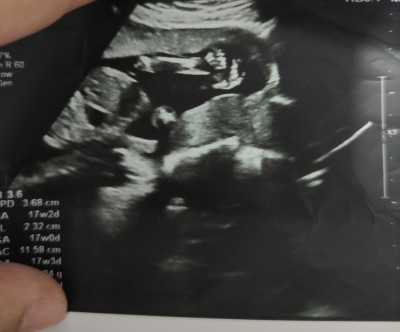

Cinsiyet tahmini alabilirmiyim kızlar doktor kıza benziyor ama tam gözükmüyor dedi

Gebelik haftası 17 hafta

Sağ taraf bacak kısmı ortada gözüken kollar eller

Icimden erkek gecti

cnm kıza benzettim